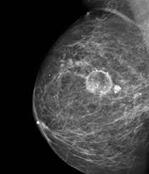

HALLAZGOS EN LA MAMOGRAFÍA

Se recomienda una mamografía craneocaudal y otra oblicua medio lateral en la primera visita. Luego se pueden hacer los controles con solo una incidencia. En los resultados de mamografía BIRADS 0 o si la mujer es menor a 35 años se recomienda la ecografía (ENARM 2022) y si esta no es confiable se indica una resonancia magnética. Los hallazgos patológicos primarios de la mamografía son las múltiples microcalcificaciones agrupadas y la masa espiculada (ver imagen) (ENARM 2014) (ESSALUD 2014). La retracción cutánea, cambios locales, vasos atípicos y cambios del pezón son signos secundarios. Según los hallazgos, se clasifica a la mamografía en el score BIRADS.

23. Signo de microcalcificaciones agrupadas y masa espiculada en mamografía

Figura